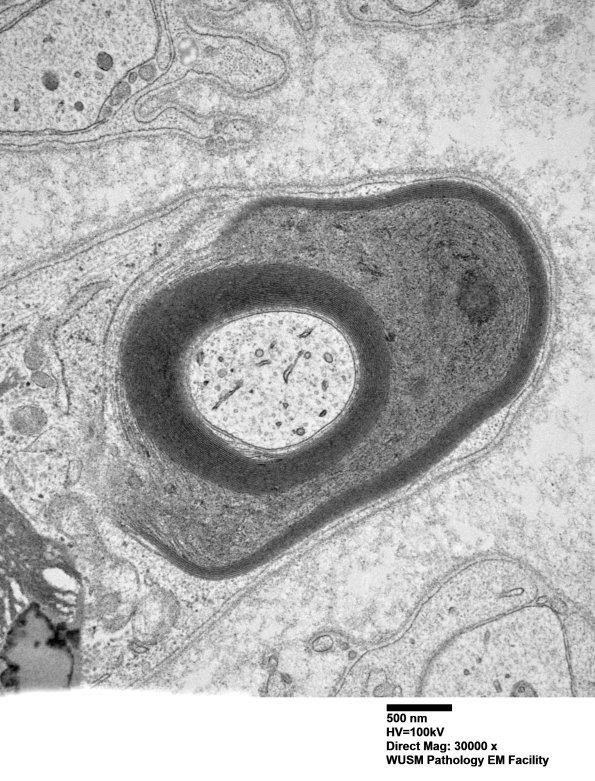

Higher magnification of image #1B6A. (electron micrograph)